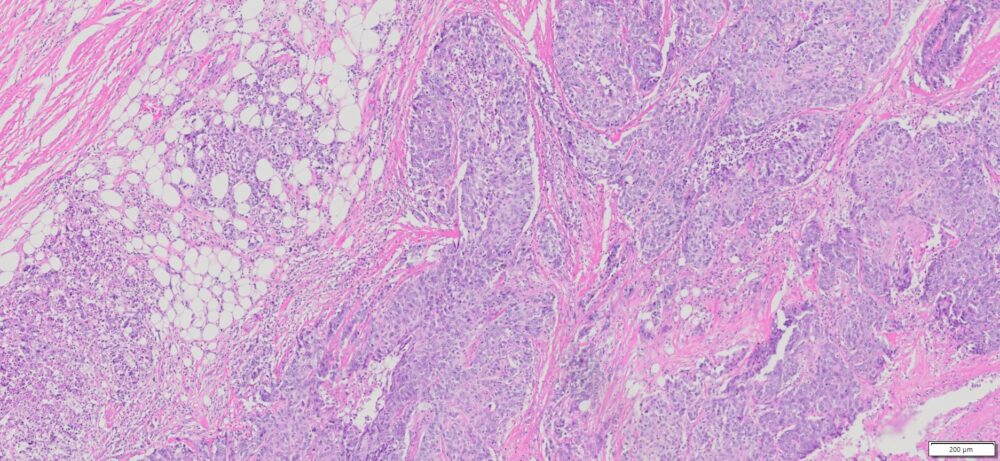

| HuPS-02037T1 | Breast | Invasive ductal carcinoma | No | Female/47 | 40% | III | NA | ER(+/-,5%)/PR(+)/Her2 (+/-Borderline), Ki67: 70% |